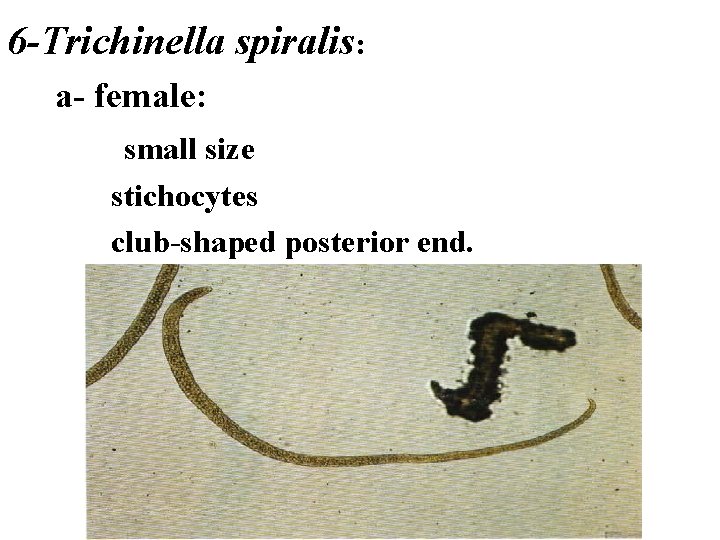

6 -Trichinella spiralis: a- female: small size stichocytes club-shaped posterior end.